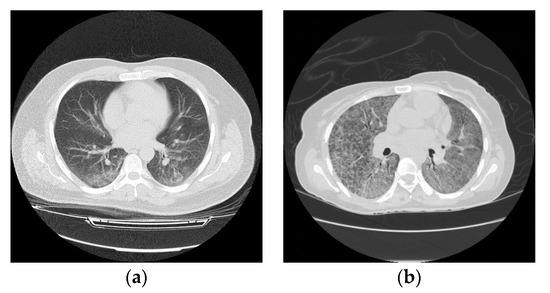

3.1. Data Collection